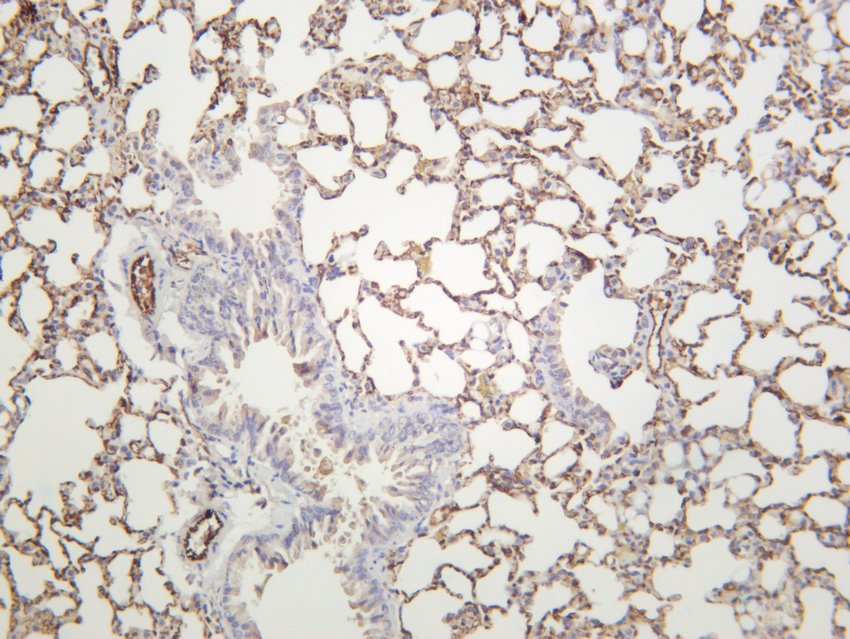

Mouse lung was stained with anti-CD31 rabbit antibody